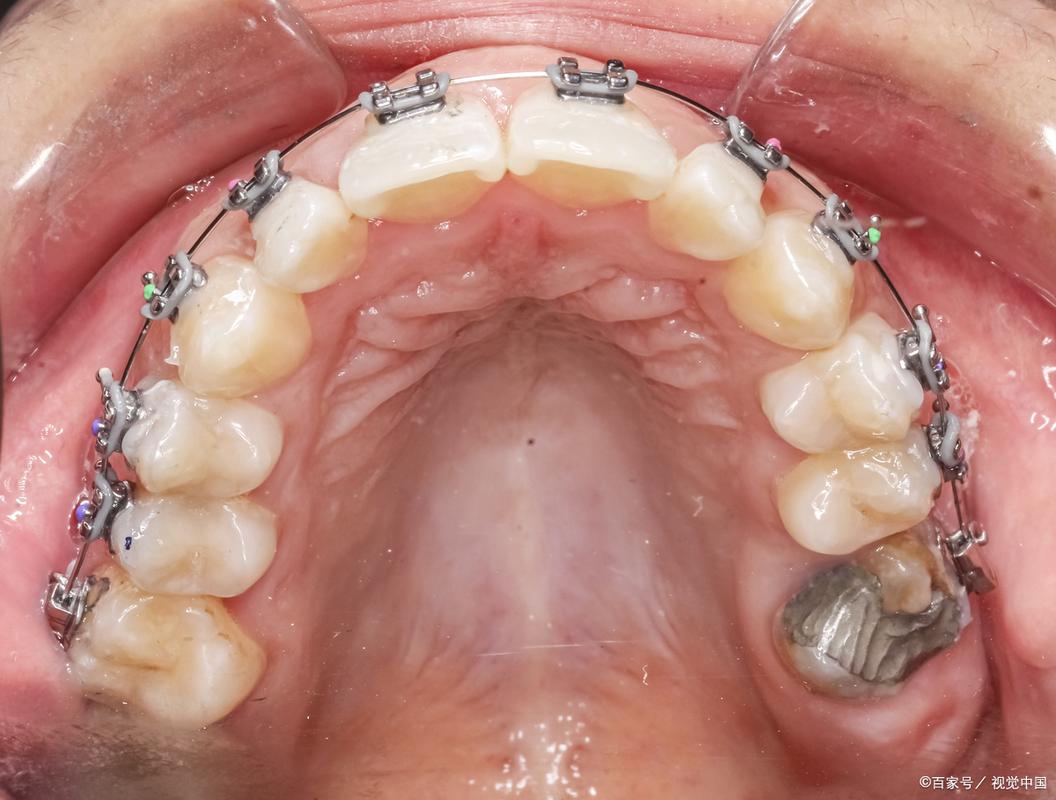

牙齿矫正(正畸)是改善错畸形、提升口腔功能与美观的重要手段,但并非所有人群都能直接接受正畸治疗,对于牙周病患者而言,正畸治疗与牙周健康密切相关,pao牙周治疗”(即牙周基础治疗,包括龈上洁治、龈下刮治和根面平整)是正畸前不可或缺的关键步骤,若牙周炎症未得到有效控制,正畸过程中牙齿移动可能加重牙周组织损伤,甚至导致牙齿松动脱落,理解牙周病与正畸的相互作用,规范开展pao牙周治疗及正畸全程牙周管理,对保障治疗效果和长期稳定性至关重要。

牙周病是由菌斑微生物引起的牙周支持组织慢性炎症性疾病,主要表现为牙龈炎症、牙周袋形成、牙槽骨吸收及牙齿松动,正畸治疗通过施加矫治力引导牙齿移动,而牙齿移动的生物学基础是牙周膜细胞的改建和牙槽骨的重建,若牙周处于炎症活动期,牙周组织对矫治力的反应异常:炎症介质会抑制成骨细胞活性,延缓牙槽骨改建;炎症可能导致牙根吸收风险增加,甚至加重牙槽骨吸收,牙周袋内堆积的菌斑和牙结石会阻碍牙齿移动,导致矫治效率降低,同时增加正畸中牙龈出血、牙周脓肿等并发症风险,研究显示,未经控制的牙周病患者正畸后,附着丧失和牙槽骨吸收的发生率显著高于牙周健康者,因此正畸前必须将牙周炎症控制在稳定期。

pao牙周治疗是牙周病的基础治疗,通过彻底清除菌斑、牙结石和牙根表面的感染牙骨质,消除牙龈炎症,使牙周组织恢复健康状态,对于计划正畸的牙周病患者,pao治疗的具体目标包括:①控制牙龈炎症,使牙龈指数(GI)、探诊出血(BOP)等指标恢复正常;②减少牙周探诊深度(PD),理想情况下PD≤3mm;③消除牙周袋,避免菌斑积聚;④平整根面,为牙周组织再附着创造条件,临床研究表明,正畸前接受系统pao治疗的牙周病患者,其正畸中牙龈炎发生率降低40%,牙槽骨吸收进展减少50%,pao治疗后需观察3-6个月,确认牙周状态稳定(无附着丧失加重,PD无加深)方可开始正畸治疗,对于重度牙周病患者,可能需联合牙周手术治疗(如翻瓣术、植骨术)以进一步改善牙周环境。

即使正畸前牙周炎症已控制,正畸过程中仍需加强牙周维护,因为矫治器(如托槽、弓丝)会增加菌斑滞留风险,同时牙齿移动本身会对牙周组织产生暂时性影响,具体管理措施包括:①强化口腔卫生指导:要求患者使用正畸专用牙刷、牙间隙刷、冲牙器等工具,每日至少刷牙3次,配合牙线清洁邻面,控制菌斑指数(PLI)≤1;②控制正畸力:采用轻力矫治原则,避免过大力量导致牙根吸收和骨吸收,每3-4个月调整一次矫治力,定期拍摄X线片观察牙槽骨情况;③定期牙周复查:每2-3个月进行一次牙周检查,包括PD、附着水平(AL)、BOP等指标,必要时进行龈下刮治;④处理并发症:若出现牙龈增生,可进行牙龈切除术;若发生牙根吸收,需调整矫治方案甚至暂停正畸。